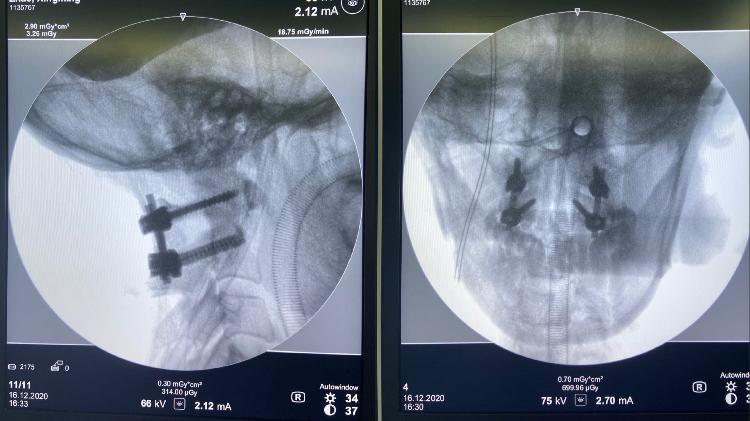

术前,汪洋医生带领团队为手术做了周密的准备,并对术中术后可能发生的问题及预防措施进行了讨论。12月16日,赵先生被推进了手术室。虽然该手术难度极高,但汪洋还是凭借精湛的手术技巧和丰富的手术经验,带领团队顺利完成了手术。手术时长1小时左右,术中出血量不到30ml。术后患者的颈痛、手麻症状明显缓解,术后复查的CT显示,寰枢关节复位效果满意。

“除了像患者这样横韧带断裂的情况以外,颅底凹陷、Jefferson骨折、齿状突骨折、枢椎骨折等都可能导致寰枢椎脱位。”汪洋表示,为了稳定上颈椎寰枢关节,我们往往会为患者行“经后路寰枢椎脱位切开复位内固定术”,“简单来说就是在脱位的寰枢椎上精准植入螺钉,将其重新固定起来,恢复其稳定性,解除脊髓压迫,即可消除症状。这个手术风险极大,所有的操作都要慎之又慎,不容一丝一毫的差错,植入的螺钉必须精准到位,否则大大影响手术效果。”